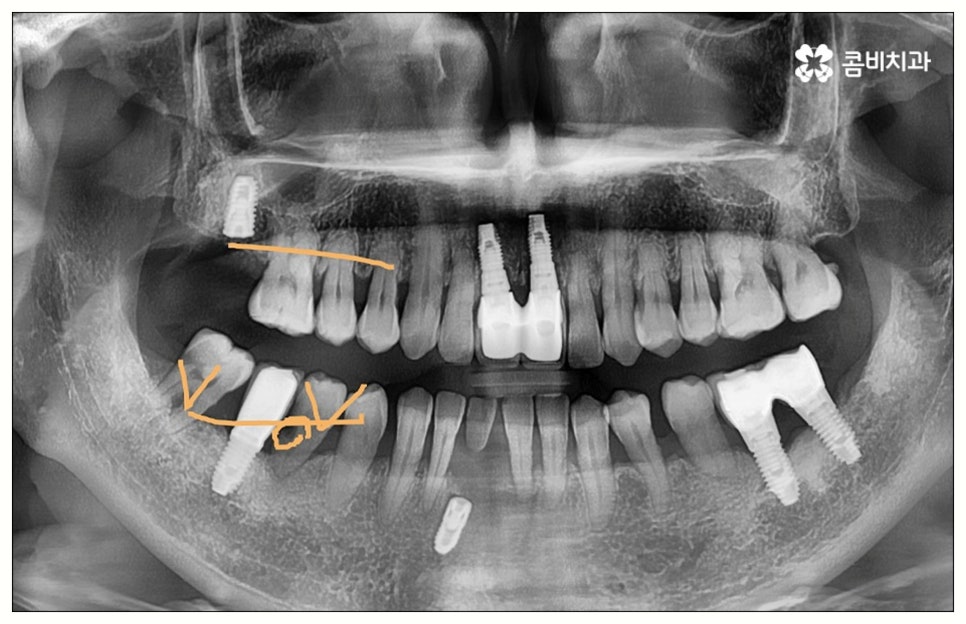

그러나 모든 환자분들이 원데이임플란트 방식을 이용할 수 있는 것은 아니기 때문에 주의하실 필요가 있어요. 말씀드렸던 것처럼 임플란트 수술은 직접 환자의 잇몸뼈에 식립을 진행하는 방식의 치료이기 때문에 잇몸뼈 상태가 양호하지 않은 분들의 경우 발치 후 바로 임플란트를 심는 것이 식립 성공률이나 지속적인 안정성 측면에서 좋지 않을 수 있어요. 특히 잇몸 질환으로 인해 염증이 심한 경우 또는 바탕이 되는 잇몸뼈의 밀도나 높이가 많이 부족한 경우에는 원데이임플란트 방식이 불가능하다고 할 수 있는데요.

이때 만약 무리하게 즉시 식립을 진행하게 되면 임플란트 치아가 제대로 기능하기 어려울 뿐 아니라 주위염 등 부작용을 일으킬 가능성이 높아 주변 잇몸 및 치아에도 좋지 않은 영향을 주게 되며 결국 임플란트가 흔들리거나 빠지면서 재수술이 필요한 상황까지 이를 수 있으므로 필요한 치료부터 선행하는 것이 좋을 거예요. 위에서 예로 든 상황이라면 잇몸 염증을 먼저 꼼꼼하게 치료한 후 또는 뼈이식술을 통해 안정성을 높인 후에 임플란트 식립을 진행하실 필요가 있어요. 이 과정에서 무엇보다 중요한 것은 수술 전 3D CT를 통해 환자의 상태를 정확하고 꼼꼼하게 확인하고, 환자의 연령, 치아를 상실하게 된 원인 및 시기, 식습관 등 관련된 모든 부분을 빠짐없이 검토하여 각자에게 꼭 맞는 계획을 세운 다음 회복 정도를 체크해 가면서 무리하지 않게 진행해 나가는 것이기 때문에 정밀 진단 장비 및 숙련된 의료진이 있는 치과에서 임플란트 치료를 받으시도록 권유드리고 있습니다.